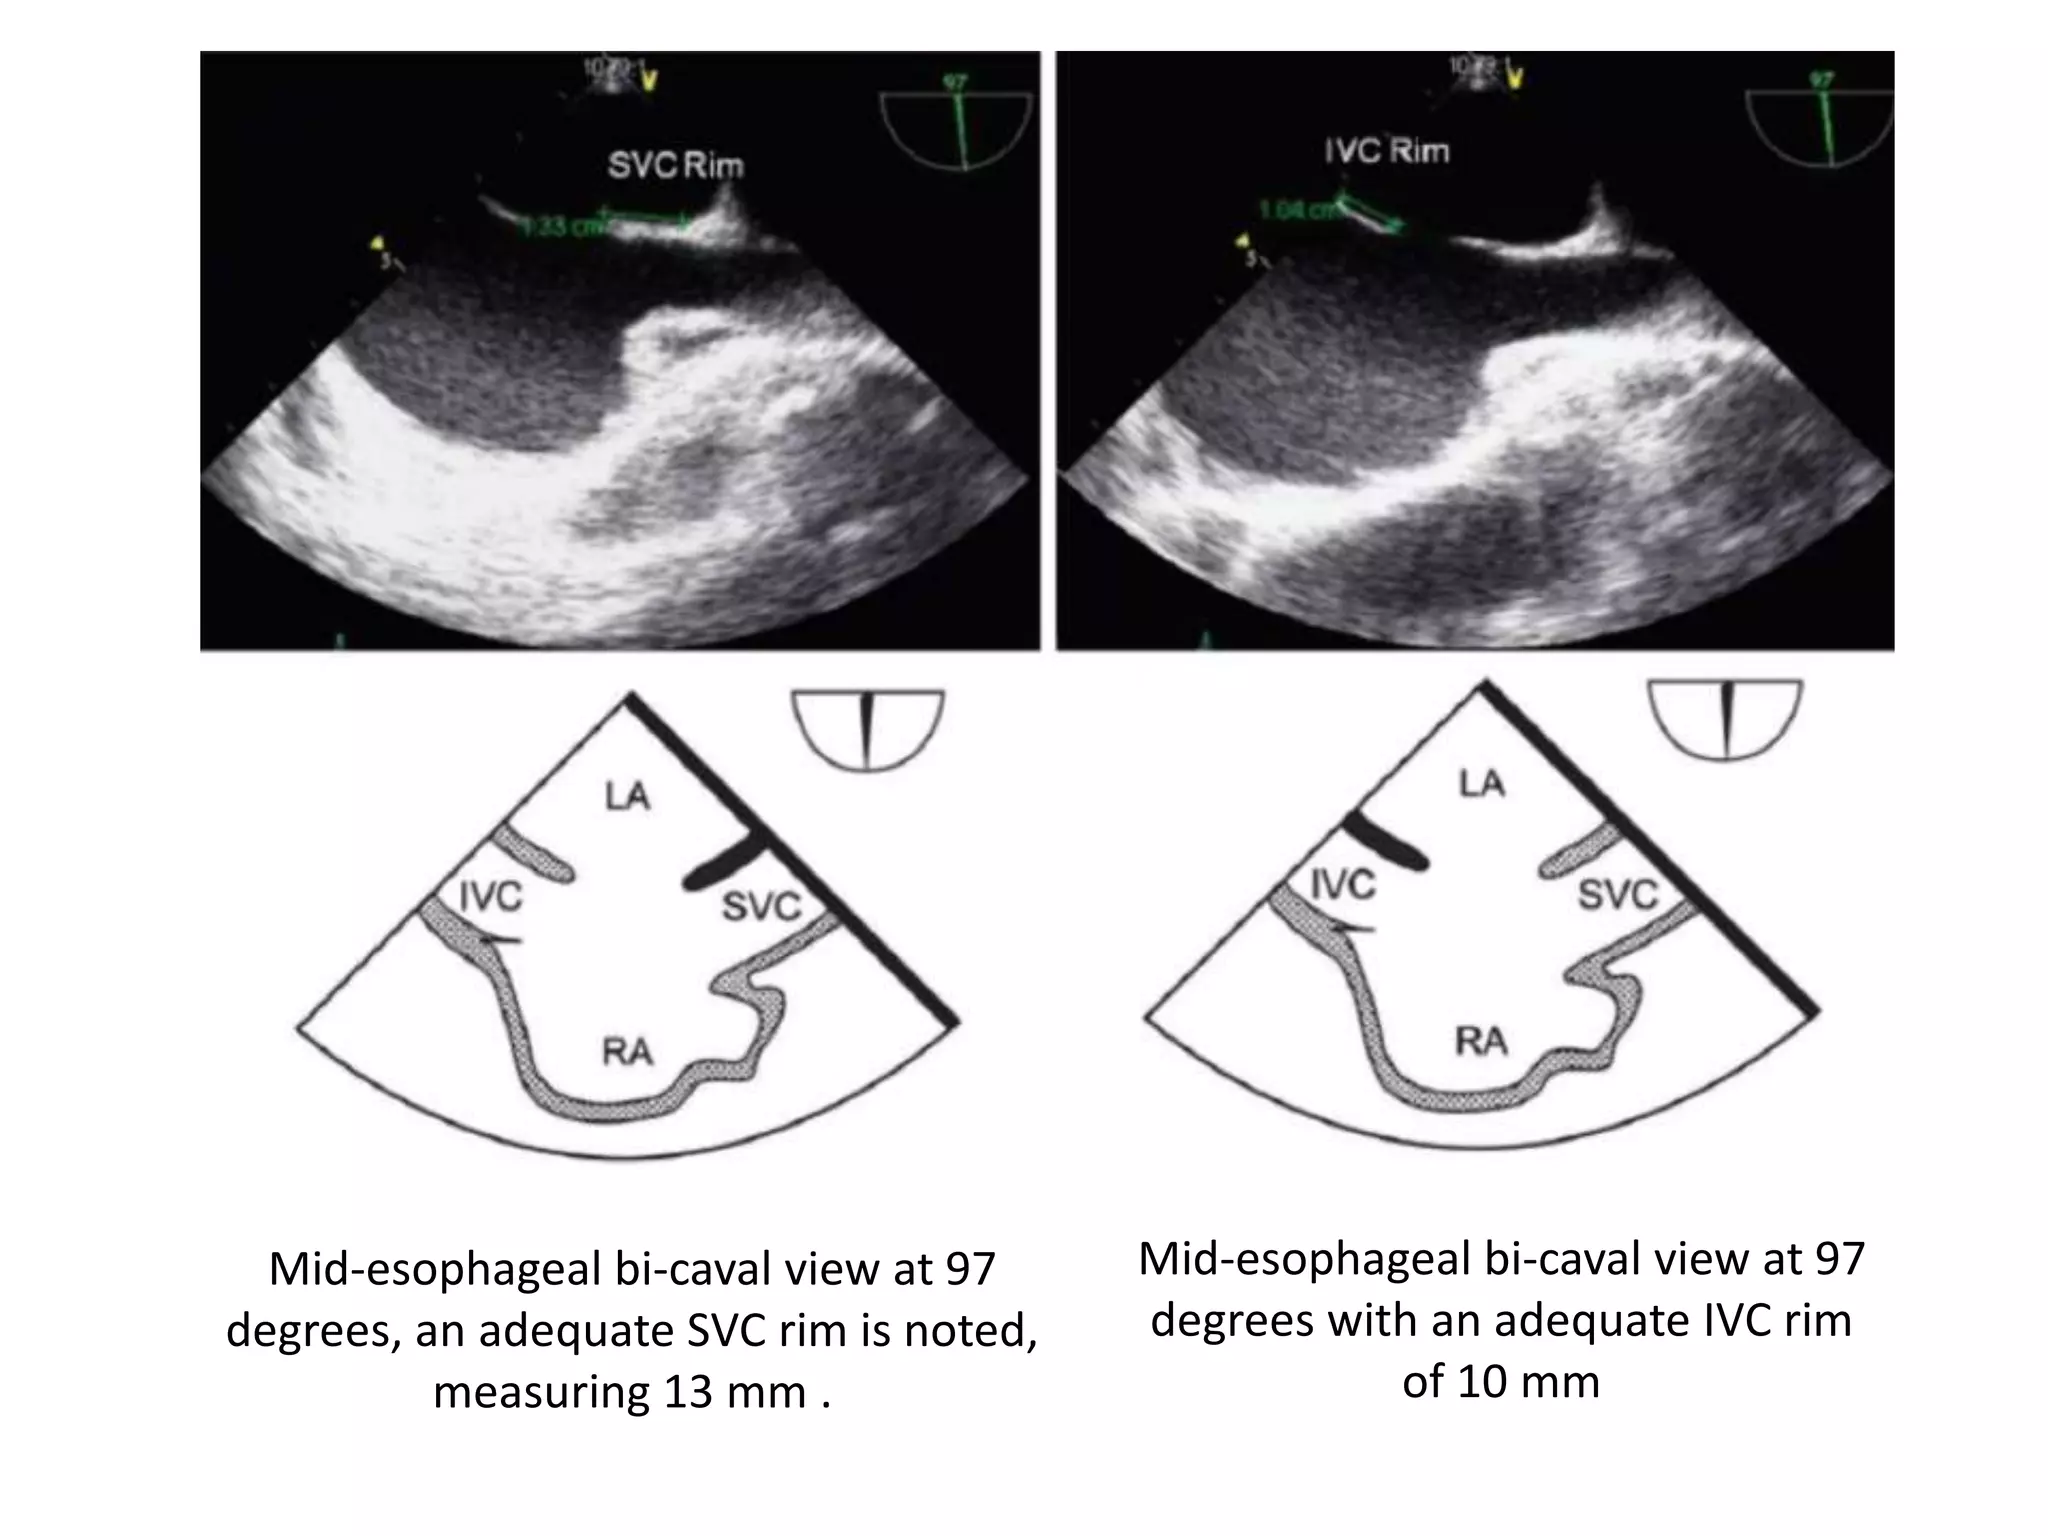

Mid-esophageal bi-caval view at 97

degrees, an adequate SVC rim is noted,

measuring 13 mm .

degrees with an adequate IVC rim

of 10 mm

Mid-esophageal bi-caval viewat 97 degrees, an adequate SVC rim is noted, measuring 13 mm . Mid-esophageal bi-caval view at 97 degrees with an adequate IVC rim of 10 mm